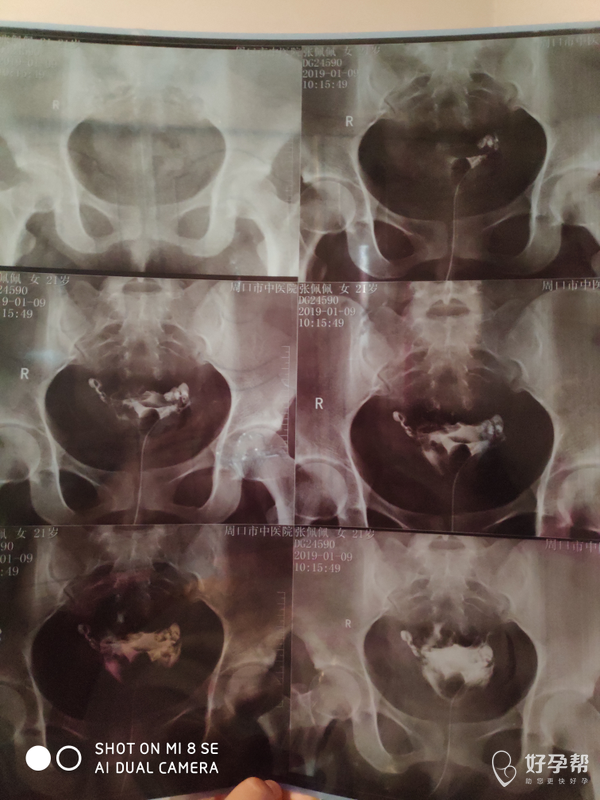

帮忙看一下 输卵管有什么问题吗

输卵管造影显示双侧输卵管是通畅的,可以2个月后备孕,排卵期在下次月经来的前14天左右,可以排卵期增加同房次数,提高怀孕机率。也可以月经期第10天开始做彩超监测卵泡,等卵泡长18mm以上为成熟卵泡,那时可以安排同房,隔天一次,看卵泡能否排出,不能排出可以肌注人绒毛膜促性腺激素10000u促进卵泡排出,可以排卵后10天化验血hcg,或排卵后14天早孕试纸测一下怀孕。祝好孕,孕前3个月至孕3个月口服叶酸预防胎儿脑神经畸形!如果我的回答对你有帮助,请采纳!谢谢